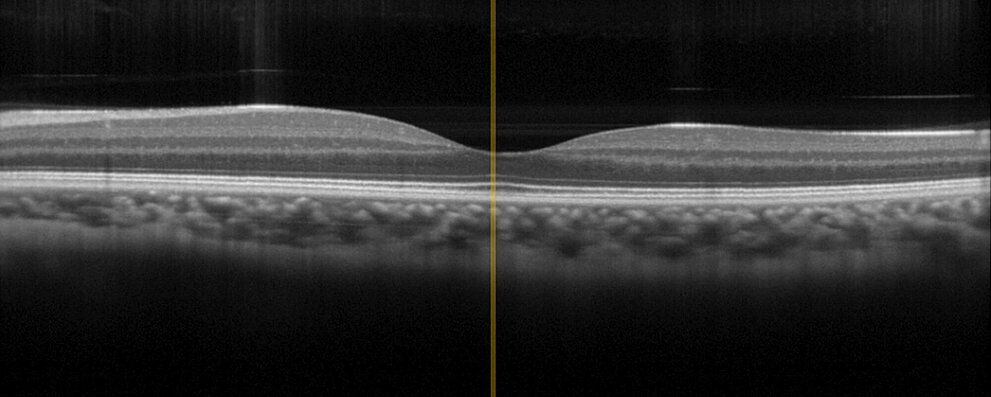

光干渉断層計 (OCT)

光干渉断層計 (OCT) は皮膚表面下の層を非侵襲的に検査し、皮膚構造の三次元画像を作成することを可能します。これには光学系の精密な調整が必要です。